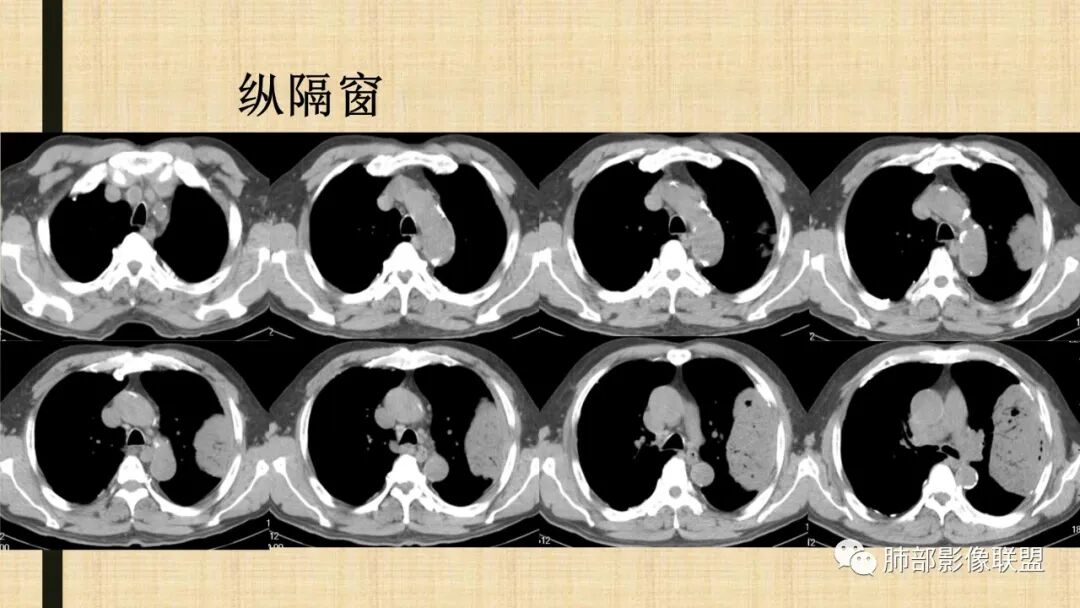

老年男性,糖尿病病史,消瘦、乏力三个月,影像表现左肺上叶胸膜下团块,有一定张力,内部疏松,可见支气管影及坏死区,增强病灶边缘环形强化,内部未见强化,考虑炎性肉芽肿病变,隐球?奴卡?放线菌?鉴别淋巴瘤。

左肺上叶胸膜下肿块,宽基底与胸膜相连,跨叶裂,边缘清晰膨隆,其内支气管充气,部分扩张、僵直,无明显强化,血管造影征,考虑淋巴瘤,鉴别腺癌

增强没有强化,血管束正常,气管束有正常有扩张,内有空洞,考虑炎性病变,隐球?

左侧胸腔巨大肿块,跨叶生长,临近胸膜钙化,边缘模糊,可见支气管影,定位肺内,增强后轻度强化,边缘见血管影,考虑淋巴瘤,鉴别肉瘤

我要修正一下观点了:仔细看了视频,肿块占位效应明显,对周围血管,支气管有推挤,增强后强化不明显,NSE增高,半年体重下降25公斤,虽然有内部支气管扩张,血管漂浮,边界清楚支持淋巴瘤,但强化太低,膨隆,占位推挤太明显(淋巴瘤一般没有这么明显的占位效应),胸膜关系有载桩,恶病质明显(乏力,半年体重下降了25公斤),NSE也明显增高,就不支持淋巴瘤了。还是考虑外朝内的恶性肿瘤,间质来源的肉瘤伴有神经内分泌分化或者大神泌。

不支持淋巴瘤的有四点:1、对周围血管支气管推挤明显。2、胸膜有栽桩,3、强化太弱(淋巴瘤一般还是中度以上甚至高度强化多见),4、NSE升高明显,体重下降太明显。

我再建一下血管。支气管进入,但是近端推移,堵塞

肺动脉推移为主,边缘部分进入

大肿块、表面光滑但深分叶,肺门侧支气管堵塞

回头看,内部支气管近端其实不连续,伴随肺动脉不存在

这两点就不符合